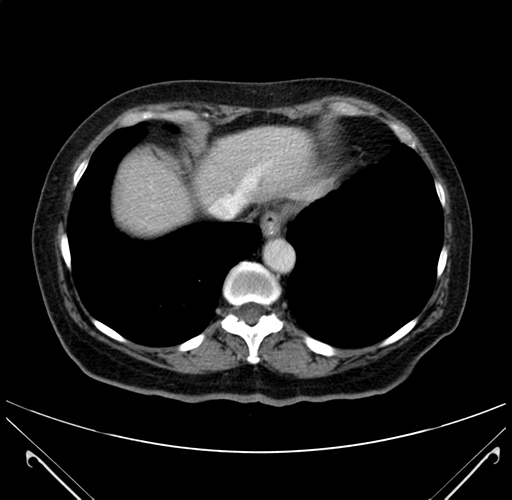

Pre-Chemo: Axial Venous

Axial Venous